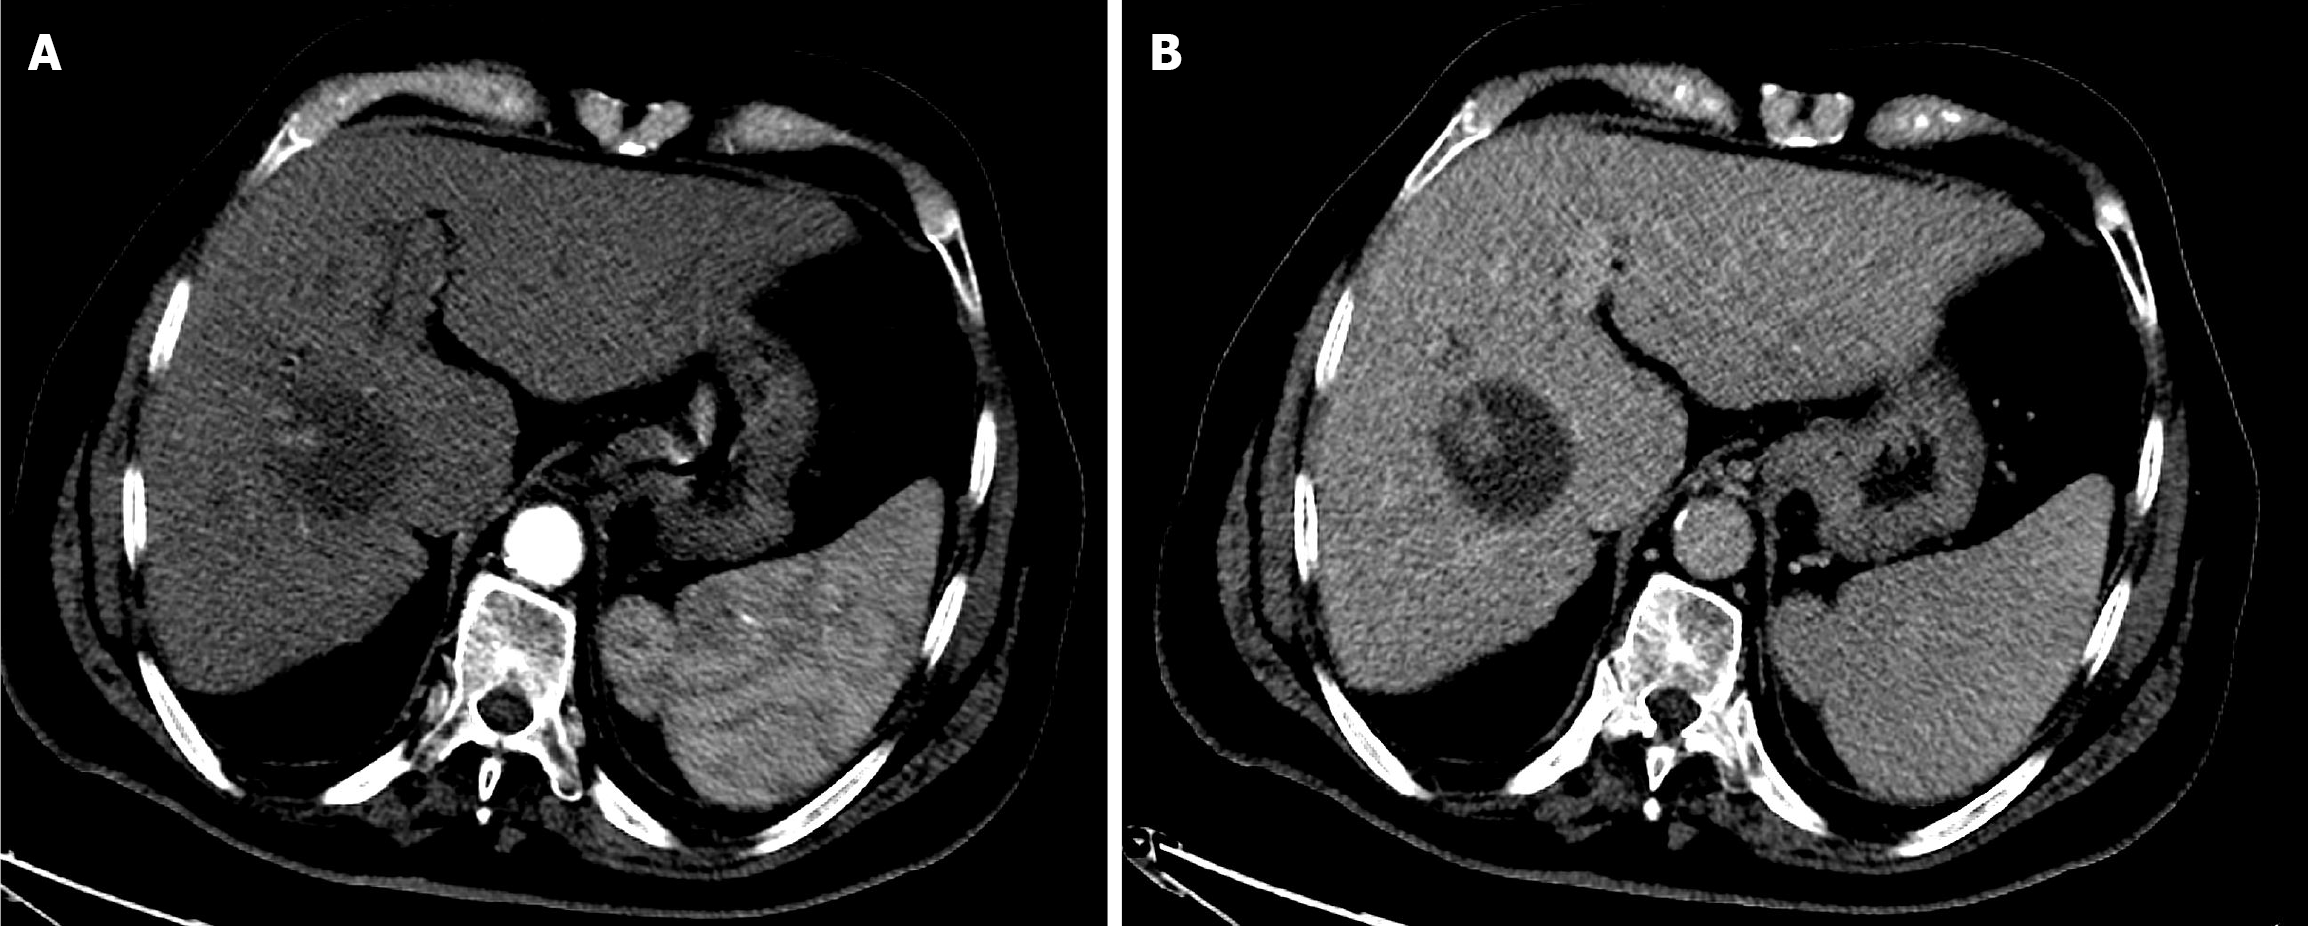

Figure 1 Baseline computed tomography of the abdomen.

A: Arterial phase computed tomography (CT) showed a large, well-defined hypervascular hepatic mass; B: Delayed phase CT demonstrated washout of the mass with an enhancing peripheral rim (tumor capsule).